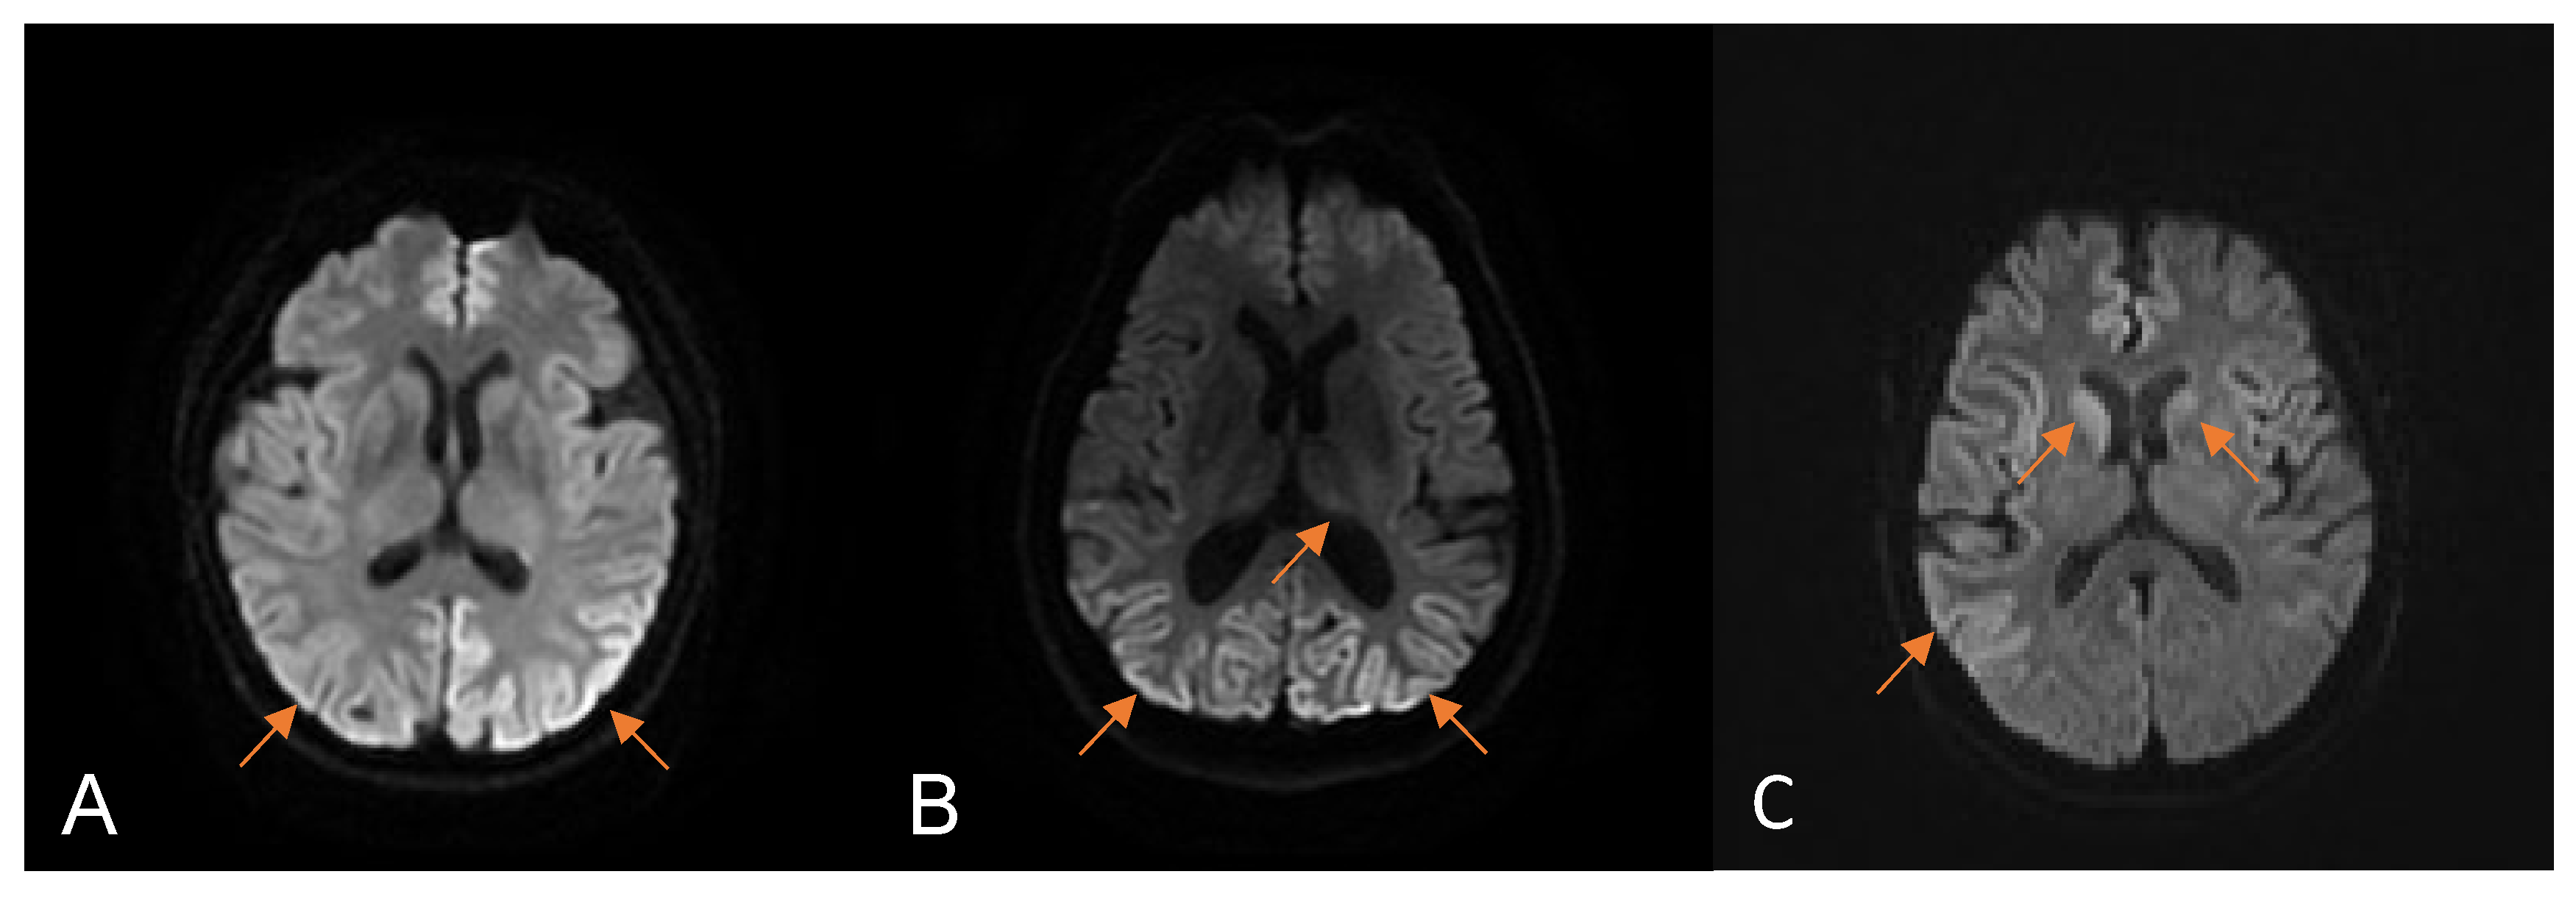

| Restricted diffusion in the first MRI, n (%) | 13 (72.2%) |

| MRI fulfilled the WHO criteria for CJD, n (%) | 10 (55.6%) |

| Restricted diffusion on occipital lobe, n (%) | 10 (55.6%) |

| Restricted diffusion in the serial MRI, n (%) | 17 (94.4%) |

| MRI fulfilled the WHO criteria for CJD, n (%) | 16 (88.9%) |

| Restricted diffusion on occipital lobe, n (%) | 14 (77.8%) |